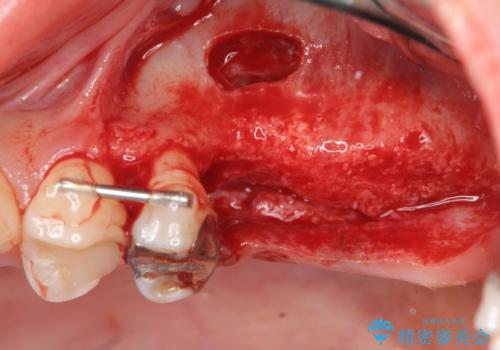

奥歯を2本失ったのち、しっかりと噛める環境へと整備するため、しっかりと骨の造成を行い清掃性を高めたインプラント治療を行っていくこととしました。

インプラントの仕上がりを見越して、ただ埋入するだけではなく長期的な予後を見込むには清掃のしやすい環境を整備することが大切です。

今回は大きく吸収してしまった歯槽骨をしっかりと造成することで、歯間ブラシを行いやすいインプラント周囲環境を整備することができました。